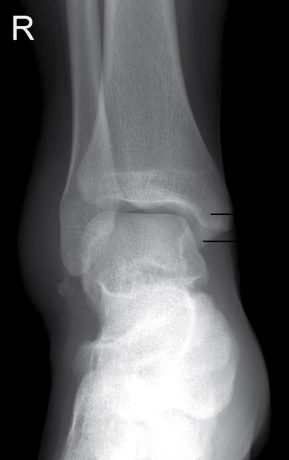

16

Q

how is ideal joint space determined for a mortise ankle

A

upper one sets the standard

17

correction

needs slightly more internal rotation

18

what ligaments would be torn here

deltoid ligaments